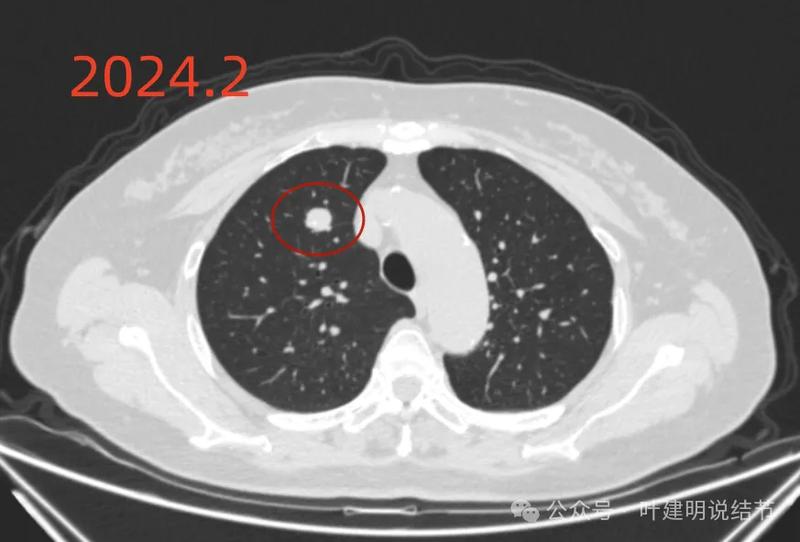

病例4:

病例5:

右上实性病灶是神经内分泌癌,考虑典型类癌。